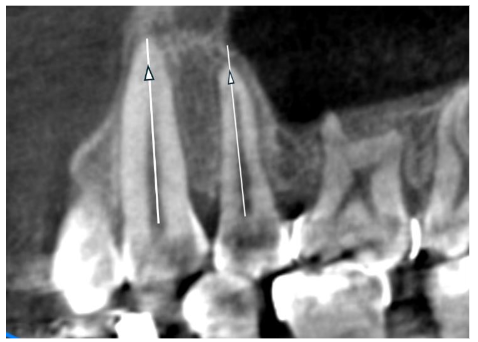

Measuring root length.

Measurements were taken after rotating the root image to display the cut vertically. The maxillary and mandibular canines and second bicuspids were measured. RCTs were performed before bracket placement, and IPR was carried out as needed to align the crowded arch. Usually, 2mm or more of enamel and dentin are removed from the mesial and distal sides. The IPR creates at least 4mm of space on each side, increasing the arch length by 8mm. Straight wire brackets were then placed, and alignment started using titanium wires. The alignment of the upper and lower teeth progressed quickly. Once a titanium wire size of 016 x 022 was reached, it was replaced with MEAW wire in preparation for the extraction procedure. MEAW wire was immediately activated after extraction to close the gap. After closing the extraction space, we placed the TADs to move the entire arch distally. At that time, CBCT was used to determine the placement of the TADs and to verify the correct implantation. In orthodontics, achieving root parallelism is essential to prevent relapses after treatment. Using the second CBCT, we evaluated the parallelism between the canine and the second bicuspid. A threshold of 5 degrees was set; cases in which the roots are not parallel and deviate by more than 5 degrees will be excluded from the study.

Checking for the roots paralleling.

There is a time difference between the canine’s coronal contact with the second bicuspid and the timing of the second CBCT. Taking the CBCT requires preparation that aligns with both the patient’s and the clinic’s schedules. The first bone density measurement was taken during the initial CBCT scan for record-keeping. The second measurement was performed on the second CBCT after the extraction site was closed. Before TAD insertion, density was measured at one-third of the root length from the apex of the distal alveolar area, likely to represent the point of highest resistance.